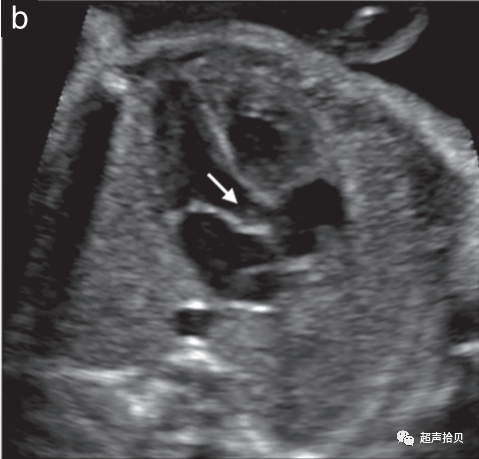

1. 在中孕期超声检查进行胎儿心脏筛查以检测先天性心脏病(图 4)。

图4 用于妊娠中期胎儿心脏筛查的代表性切面。确定心脏部位,胎儿胃和胎儿心脏在同一左侧位置(未显示)。

(a)四腔心切面 (4CV)包括两个心房,左侧和右侧(LA 和 RA),以及两个心室,左侧和右侧(LV 和 RV),并列的房室瓣和完整的室间隔。

(b)左心室流出道(b)(箭头)和右心室流出道(c)(箭头)。两条动脉流出道的大小大致相等,并且在正常胎儿中通过彼此交叉离开各自的心室。

(d)三血管切面(肺动脉(Pa)、升主动脉(Ao)和右上腔静脉(SVC))和三血管-气管切面(e)(导管弓(Da)、主动脉弓(AA)、右上腔静脉 (SVC) 和气管 (Tr)) 。

1. 胎儿心脏的超声检查从胎儿心脏四腔心切面开始。

2. 常规心脏筛查还应评估主动脉和肺动脉流出道,以检测超出仅使用四腔切面可实现的心脏畸形(图 4a)。外观正常的大血管大小大致相等,当它们离开各自的心室时应相互交叉(图 4b,c)。除了四腔切面外,对心脏流出道的常规评估提高了识别圆锥干异常的筛查性能,例如法洛四联症、大动脉转位、右心室双出口和共同动脉干畸形。

3. 三血管切面和密切相关的三血管气管切面可以改善流出道、主动脉弓和全身静脉异常的检测(图 4d、e).